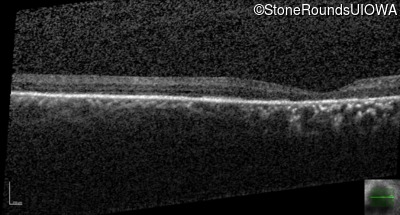

The clinical features supporting the diagnosis of Bardet Biedl syndrome in this patient include: bone-spicule-like pigmentation, narrowed arterioles and macular atrophy on ophthalmoscopy; photoreceptor loss on OCT; ulnar polydactyly, obesity, abnormal cognition, hypertension; and, normally sighted parents.